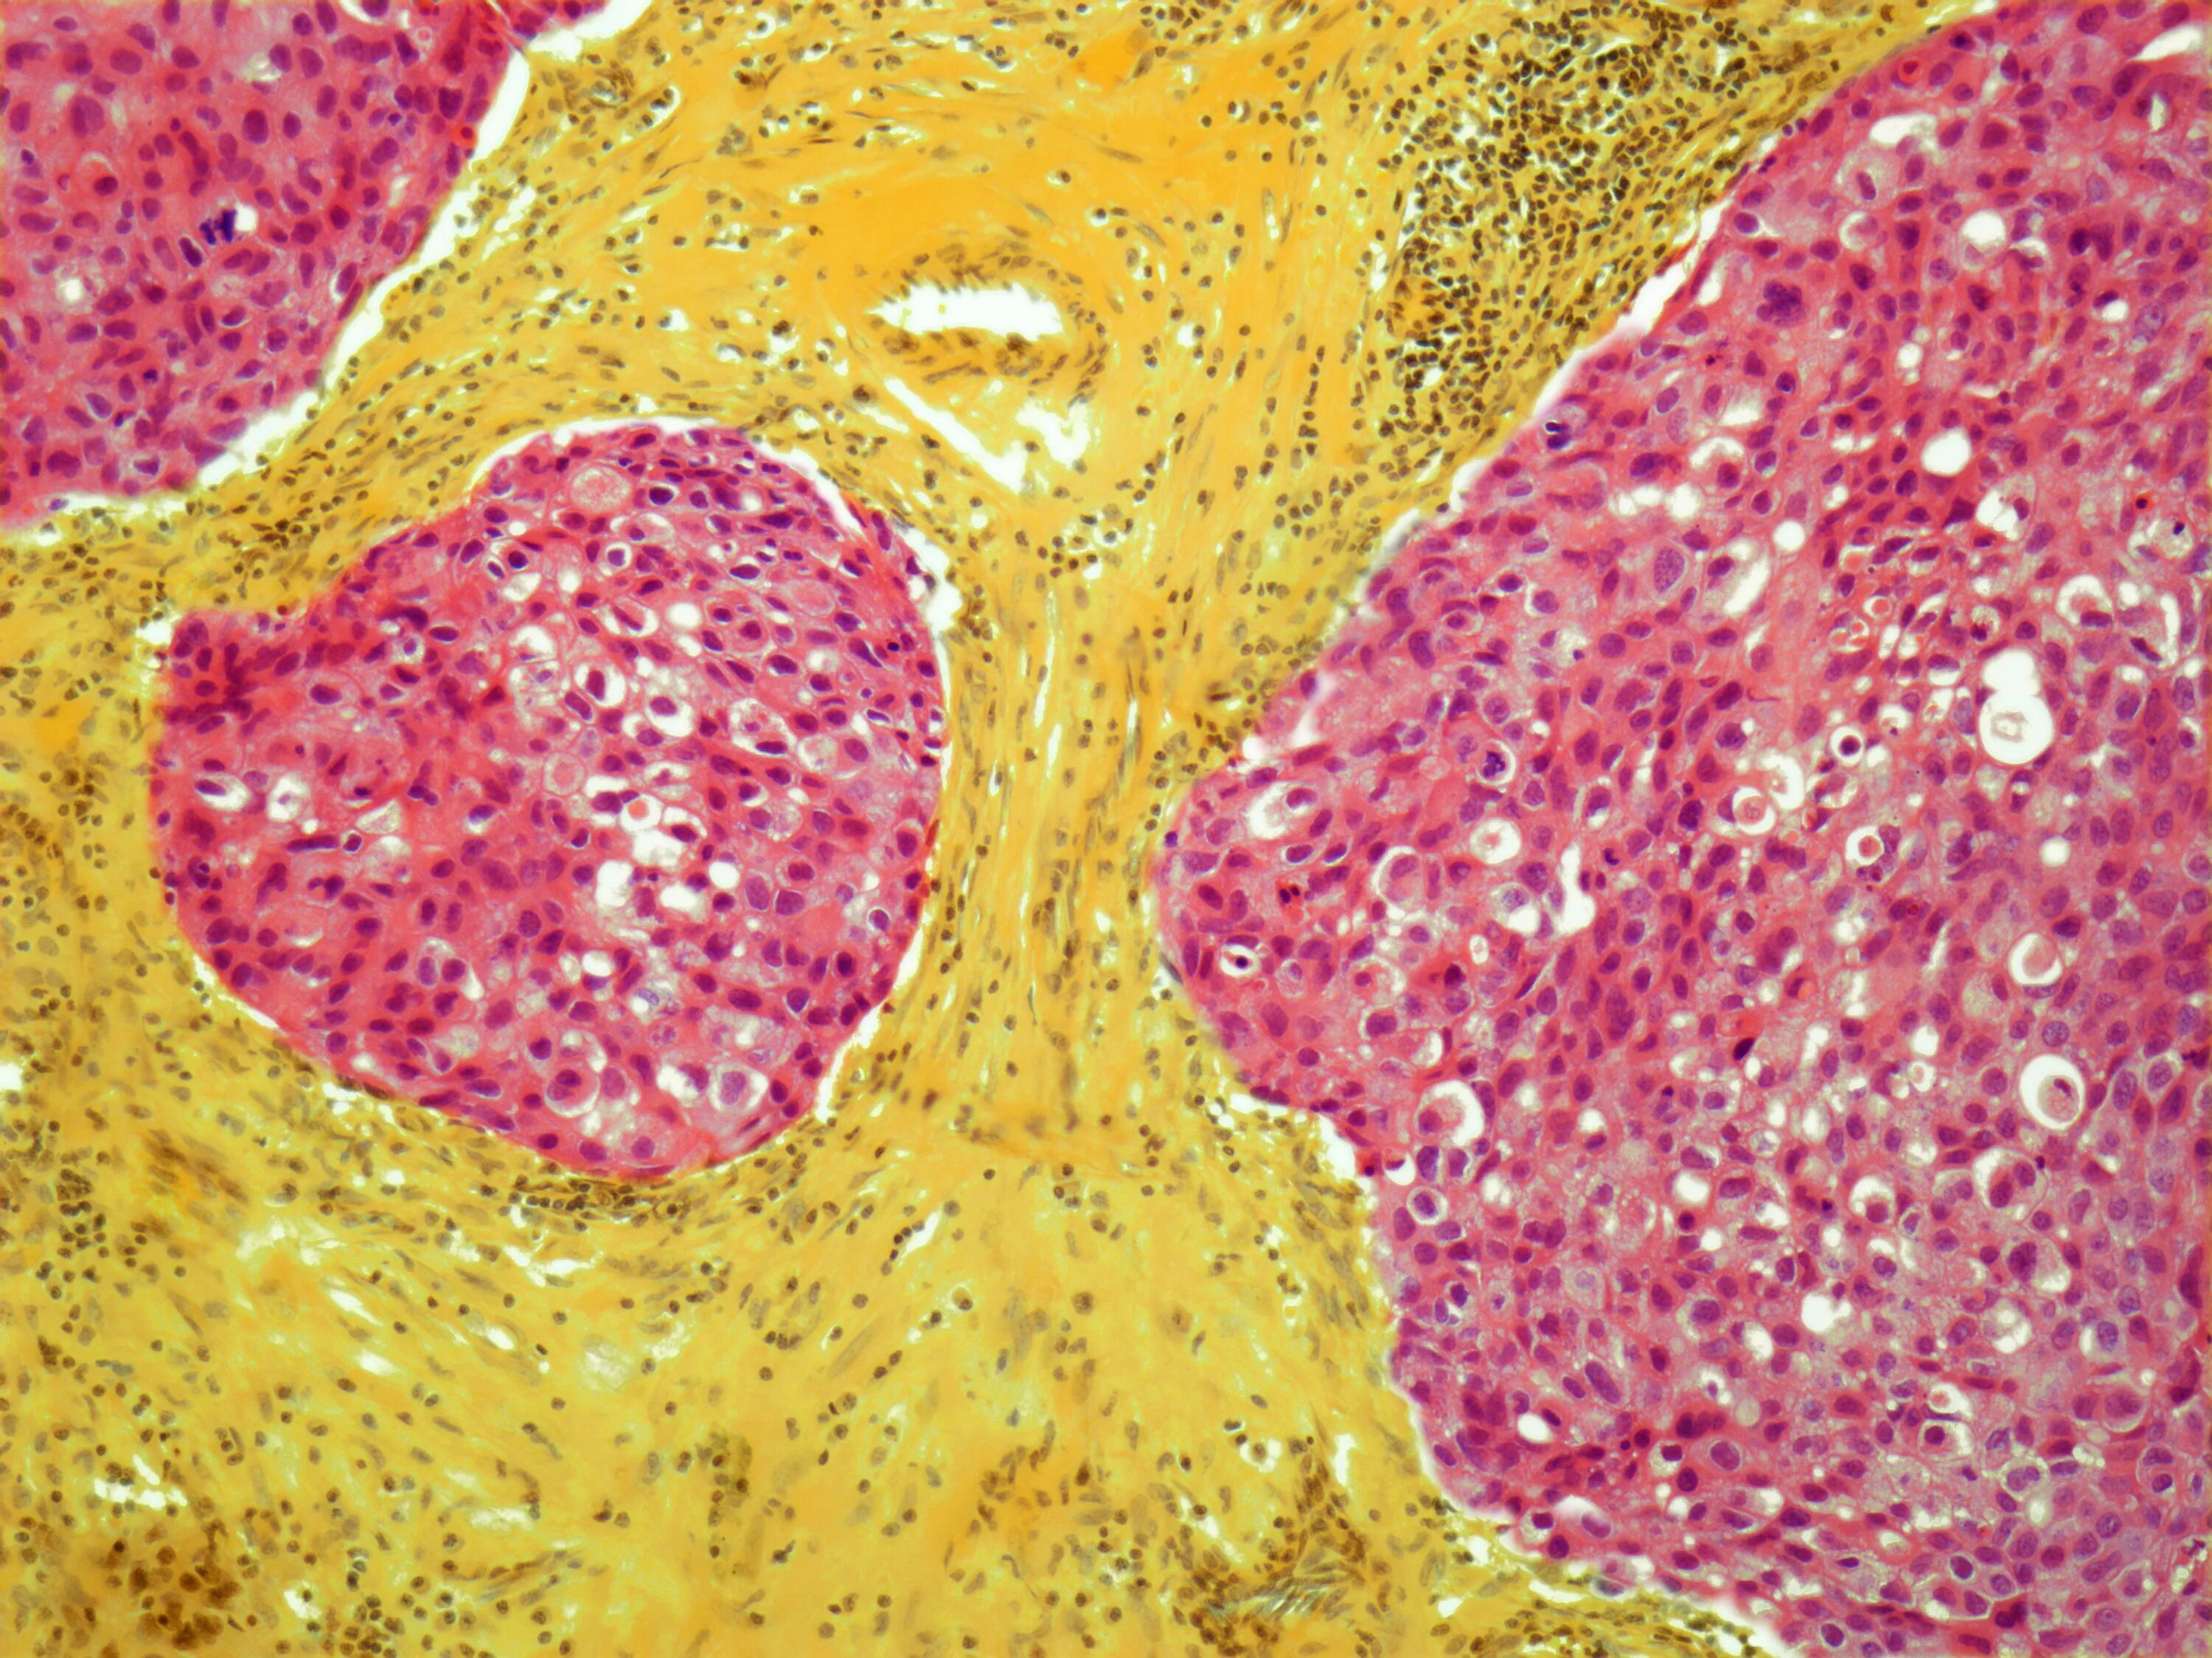

Метастазы в молочную железу